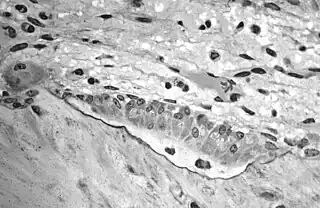

In histology, osteoid is the unmineralized, organic portion of the bone matrix that forms prior to the maturation of bone tissue.[1] Osteoblasts begin the process of forming bone tissue by secreting the osteoid as several specific proteins. When the osteoid becomes mineralized, it and the adjacent bone cells have developed into new bone tissue.

Osteoid makes up about fifty percent of bone volume and forty percent of bone weight. It is composed of fibers and ground substance. The predominant type of fiber is type I collagen and comprises ninety percent of the osteoid. The ground substance is mostly made up of chondroitin sulfate and osteocalcin.